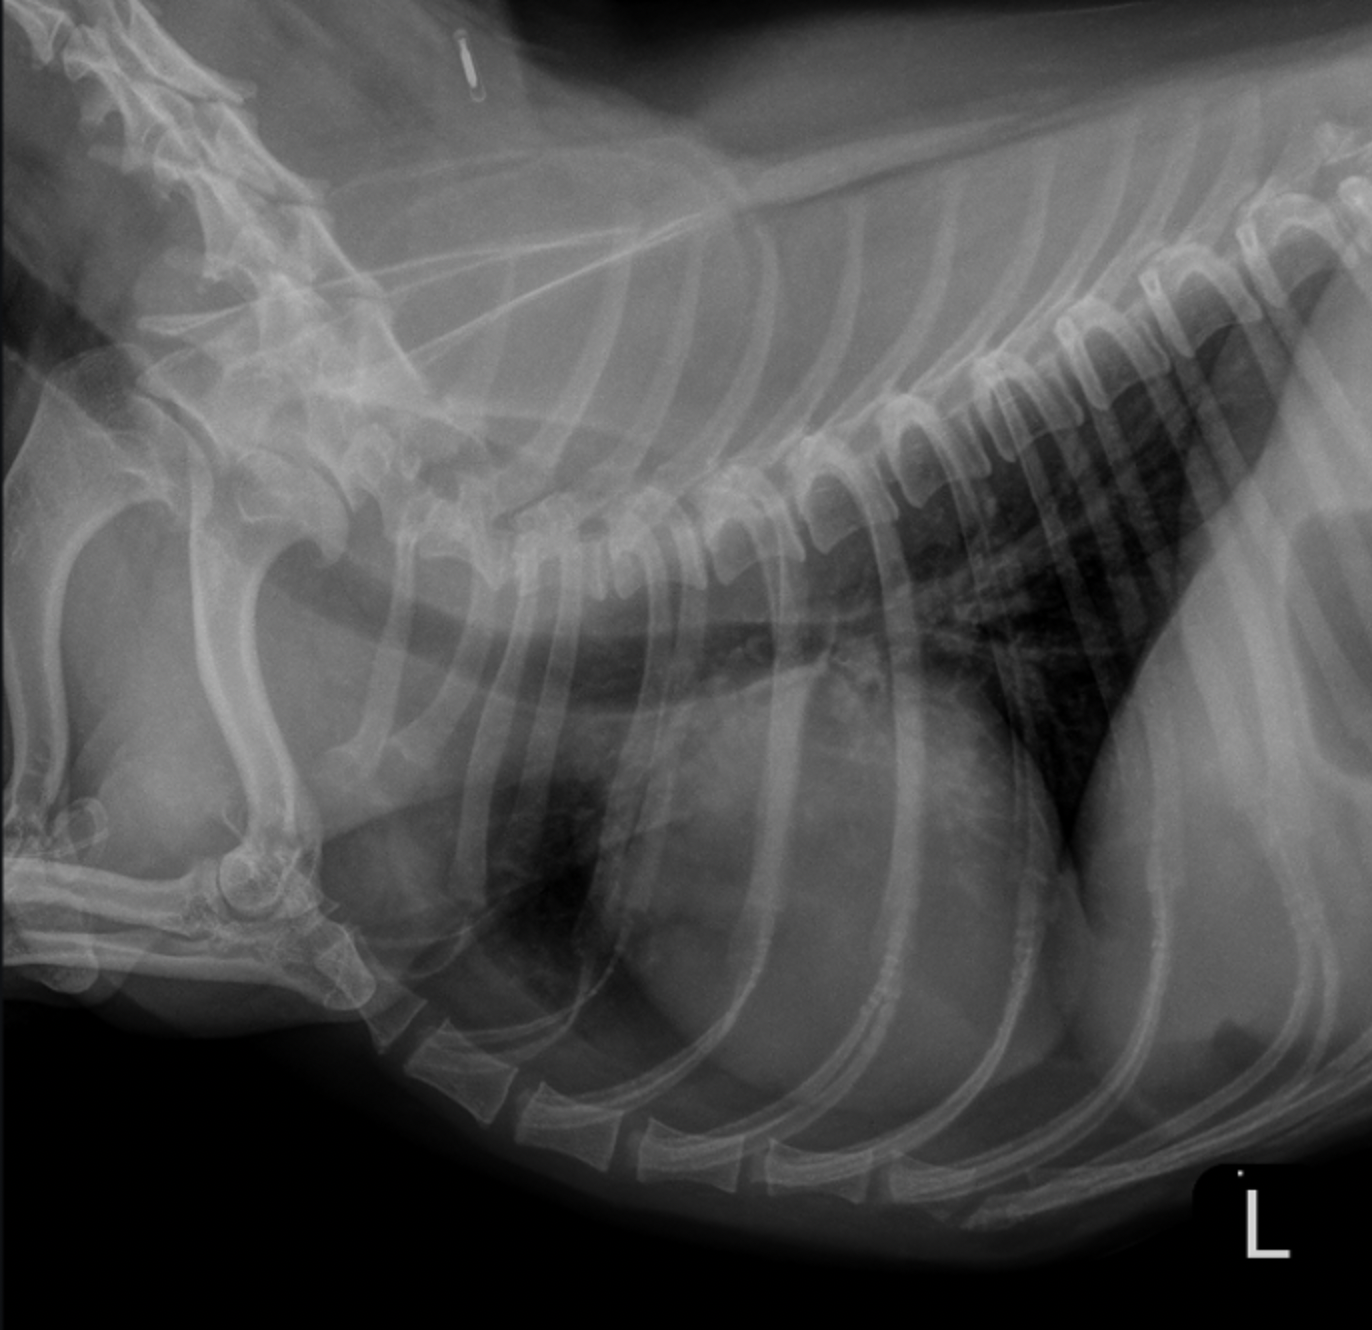

This is my baby, Fenrir. On Saturday, 11/8/25, he suddenly got sick around 1 pm, threw up, and inhaled his own vomit. After about 20 minutes, his breathing became labored. After asking advice from friends in the field, we immediately rushed him to an ER vet. He was immediately taken from us upon arrival, and placed into a special clean oxygenated room. Where he was placed on 100% Oxygen. We learned that after he threw up, he aspirated aka (sucked fluids into his lungs), causing immediate aspiration pneumonia. This is a serious, painful lung infection that’s making it hard for him to breathe.